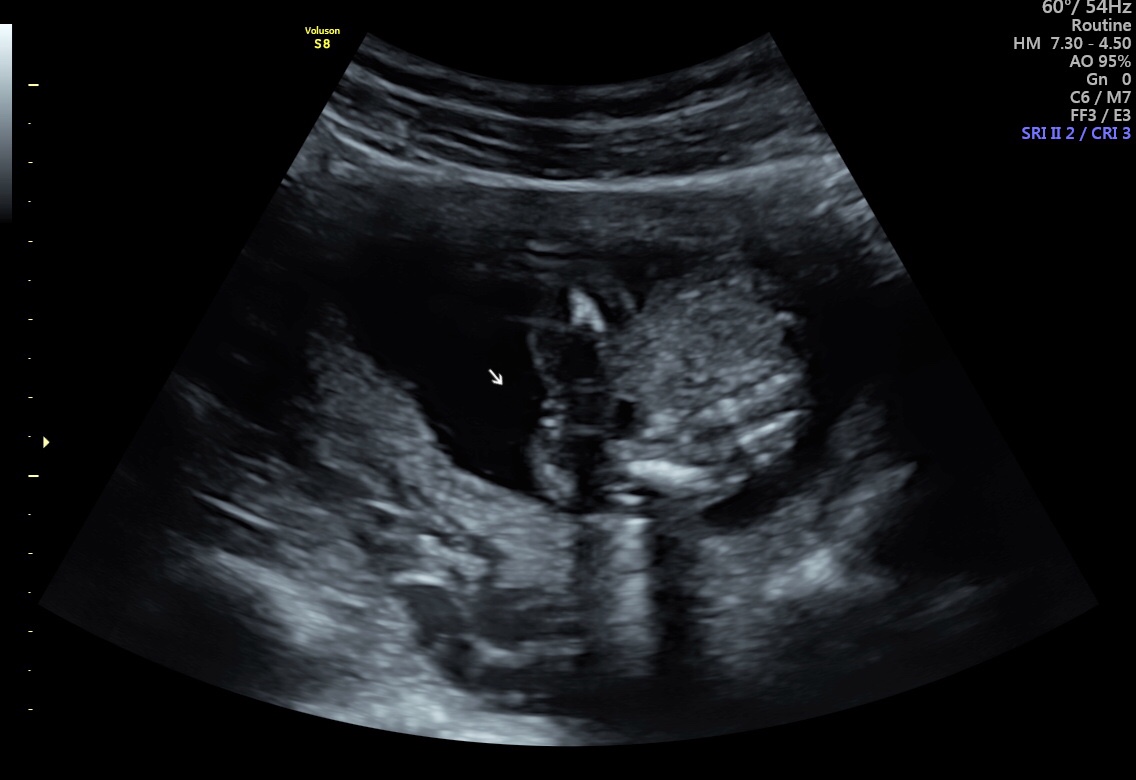

We had our 16 week ultrasound a few weeks ago and I keep worrying that the sonographer might have got it wrong. We got lots of pictures. Some look girly and others I’m not so sure. What do you all think? Attachment 39988